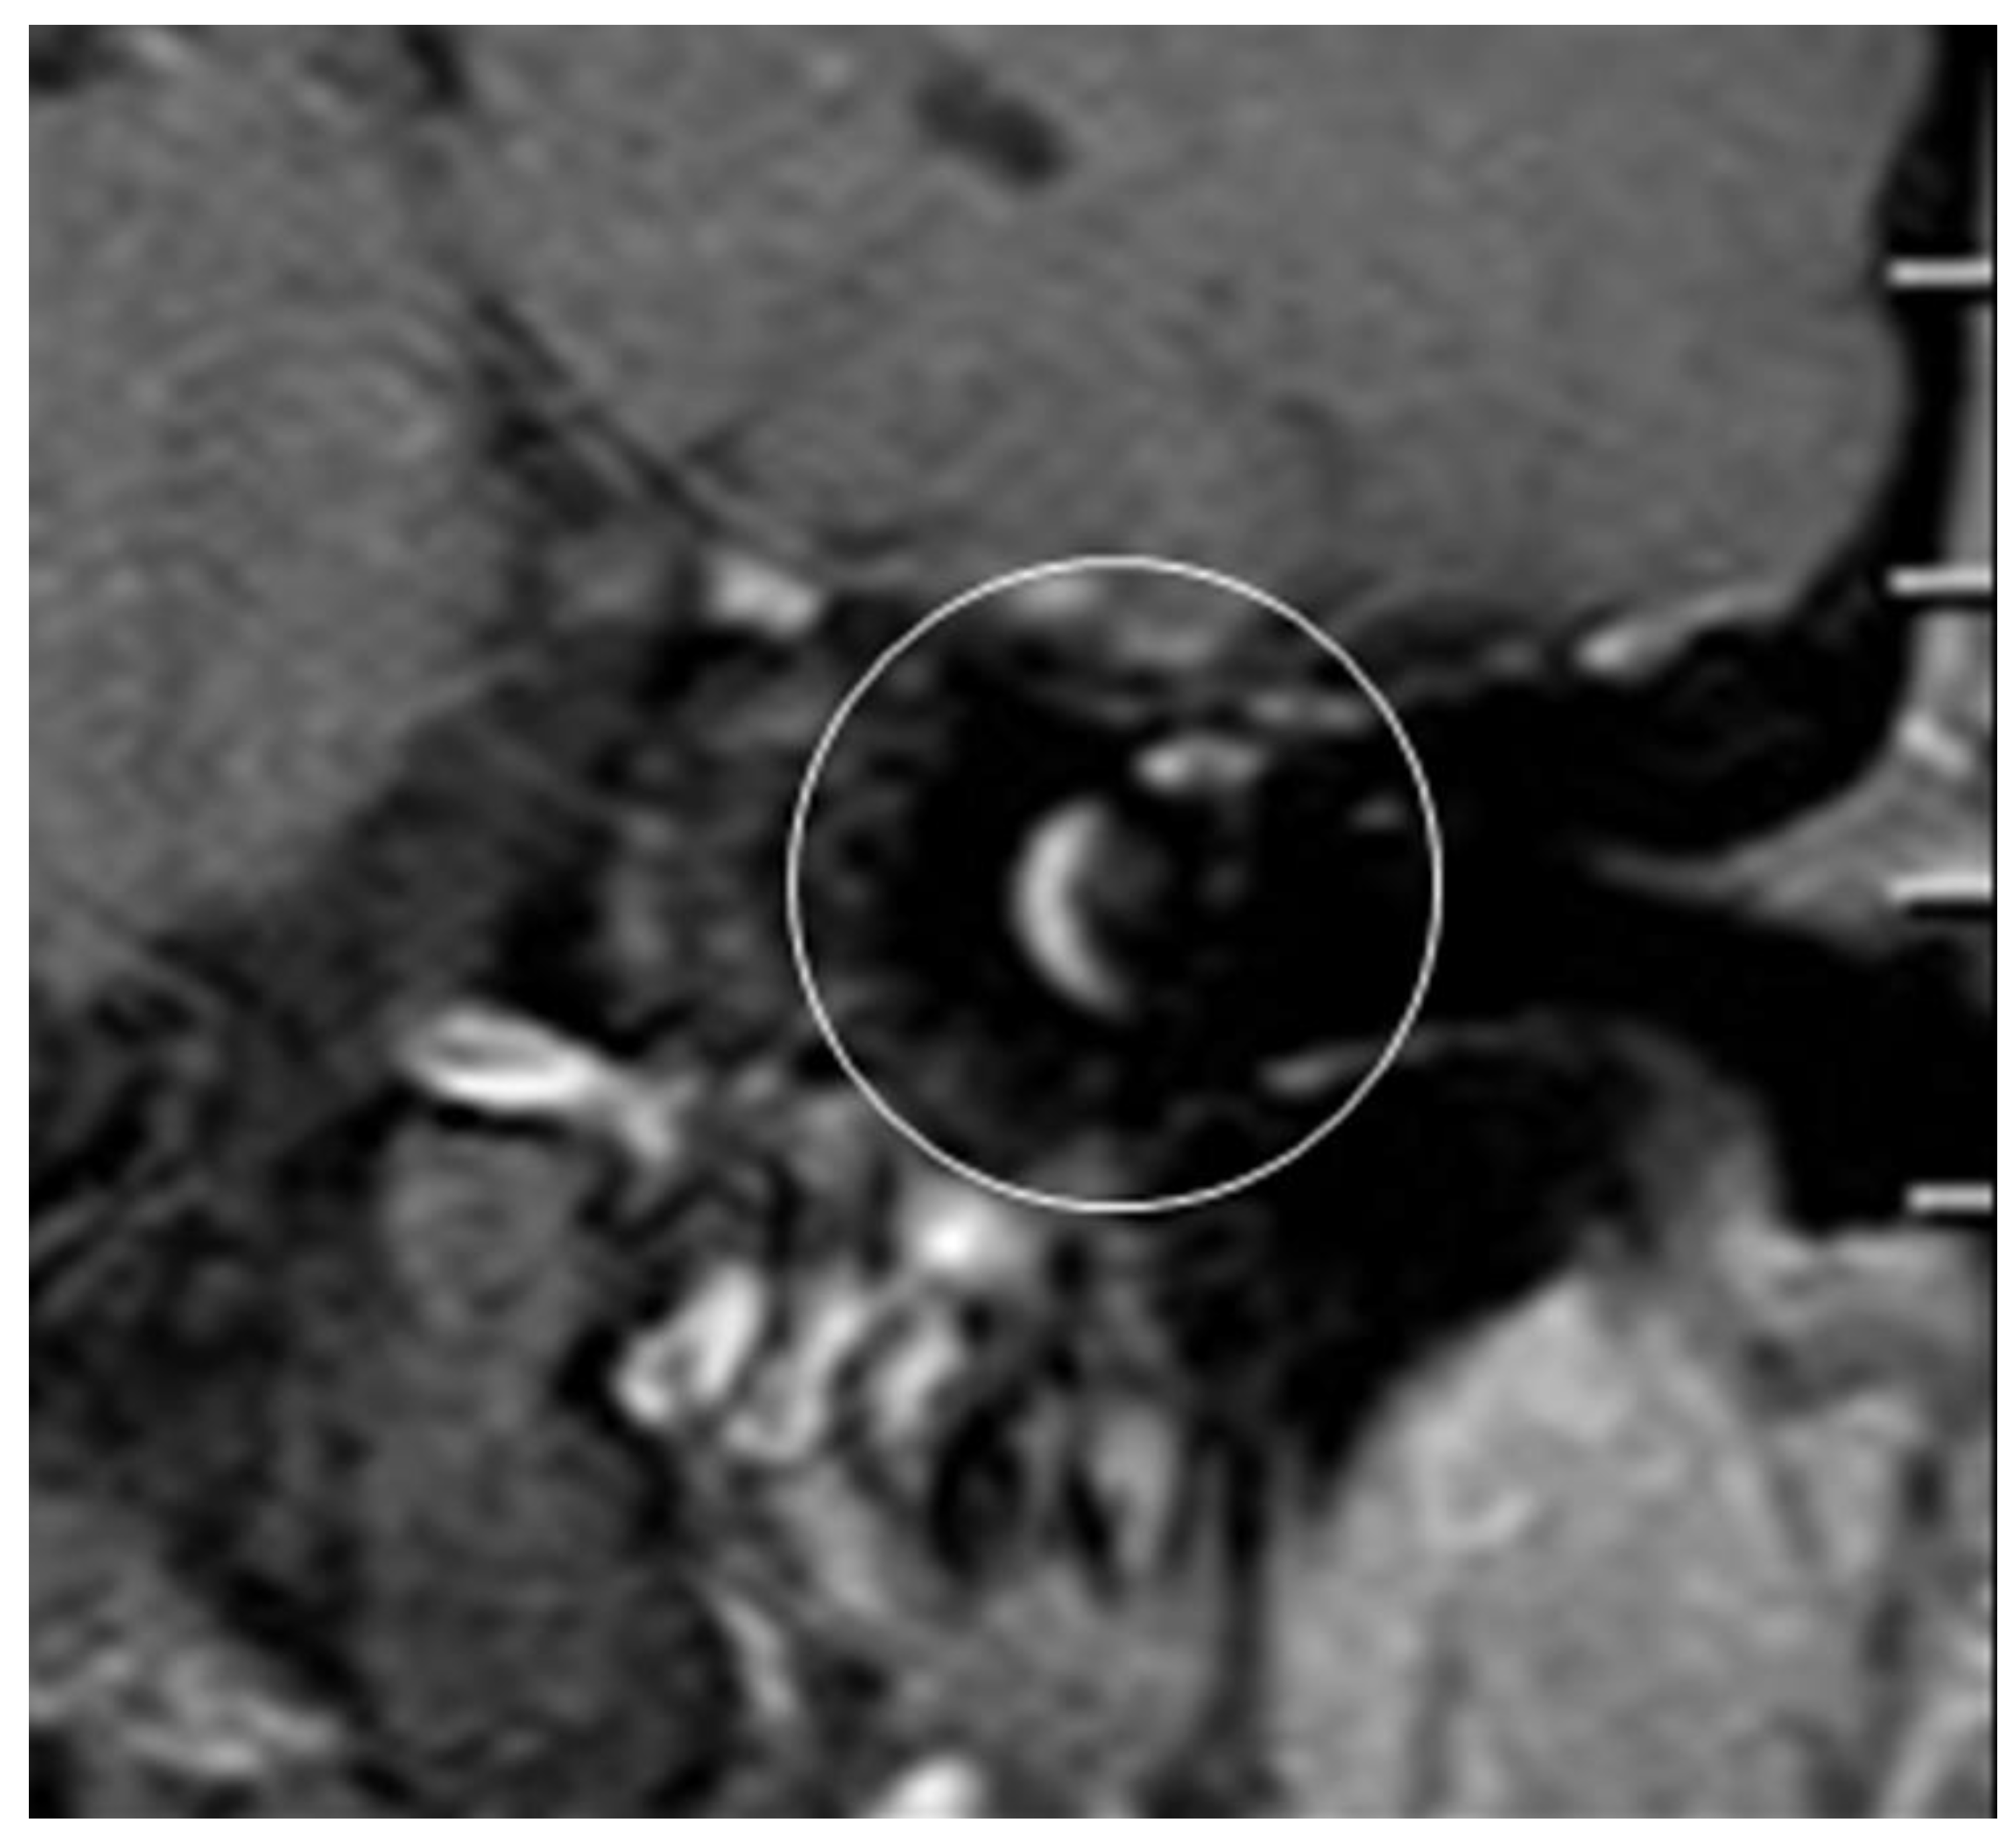

After the removal of parts of the tumor through the enlarged cochleostomy (Figure 1) the TRD was introduced (Figure 2) until the tip was visualized (Figure 3) and carefully grabbed out of the second turn access. By grabbing the tip, the device slipped into the cochleostomy and pushed parts of the tumor out of the second turn. Residual tumor parts could be detached by pipe cleaner handling (Figure 4) and sucked out (Figure 5).

The whole procedure lasted 15 minutes in each case. Comparing pre-OP (Figure 6) and post-OP (Figure 7) MRI scanning confirmed a complete removal of the tumor.

Figure 6. a, b: Pre-OP MRI.

Preprints 103791 g006

Figure 7. a, b: Post-OP MRI.

Preprints 103791 g007